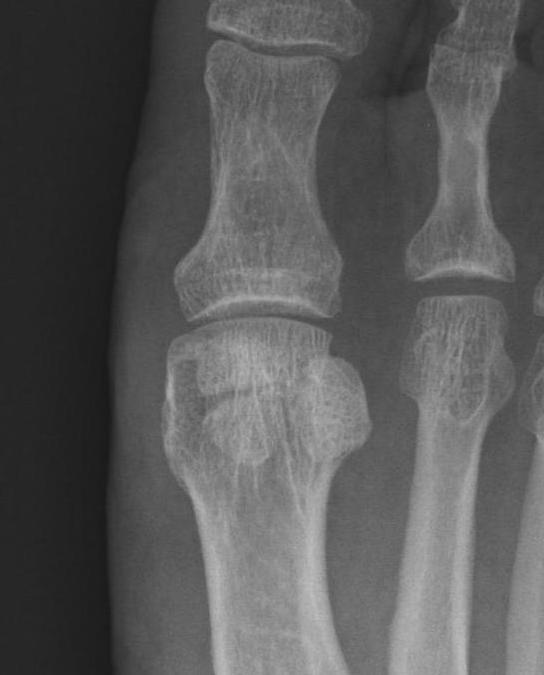

Imaging

Bilateral standing xray can help

Unclear if bipartite or stress fracture

Irregular borders suggest fracture rather than bipartite

CT demonstrates irregular borders consistent with fracture of tibial sesamoid